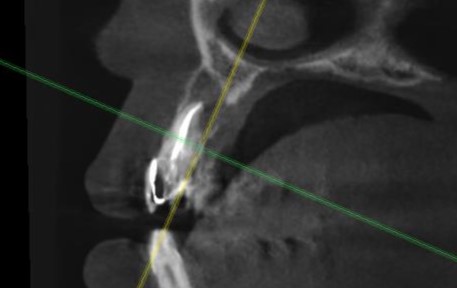

Киста в области зуба 2.1